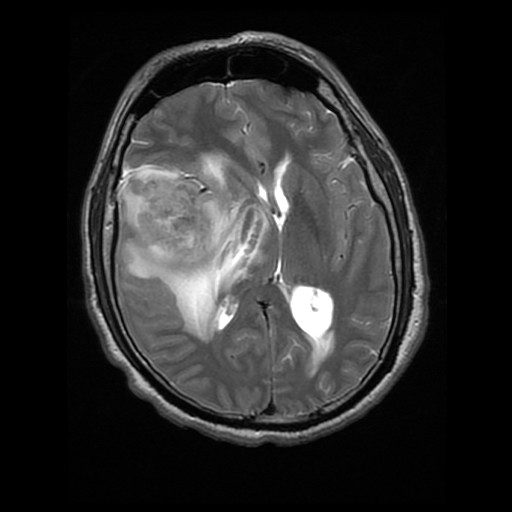

History:  The patient was a 43 year-old man who complained of a 4 week long history of nausea, vomiting, and headache with pain in the central forehead area. He reported also a 6 day long severe pain and dizziness so severe that he could not leave home. His neurological examination was free from focal signs or weakness. An MRI scan demonstrated an avidly enhancing mass, 5.2 x 4.4 x 4.9 cm, in the right frontal parietal area that was most likely extra-axial and with dural tail enhancement. There is substantial edema around the mass as demonstrated on FLAIR images. The mass was excised and yielded the specimen being shown here.

• On T1-weighed images, he tumor mass show heterogeneous enhancement with dural tail enhancement. There is no definitive ring enhancement. The mass is large enough to cause midline shift and compression of the lateral ventricles. The tumor is rather well demarcated overall. FLAIR images demonstrate a substantial amount of edema around the tumor.

• On T2-weighed images, there is partial CSF crest formation at the frontal area where the tumor is close to the dura.

• The overall features suggest a meningioma but other primary tumor cannot be ruled out.